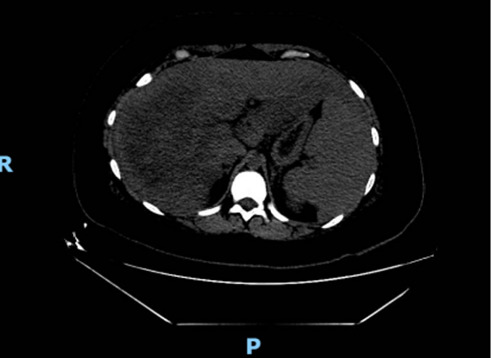

Abstract Image